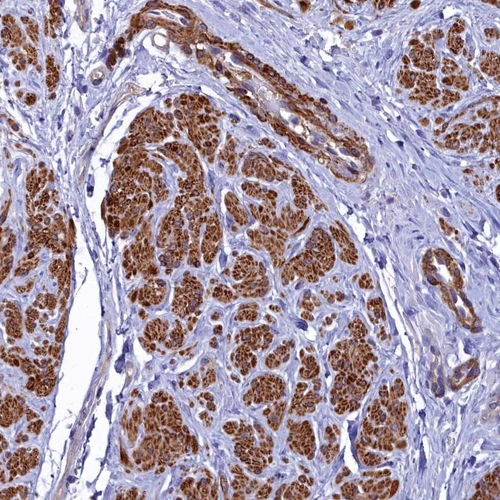

Immunohistochemical staining of human smooth muscle shows strong cytoplasmic positivity in smooth muscle cells.